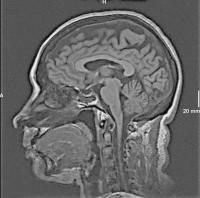

Abbildung 1: Die t1-gewichtete MRT des Gehirns in median-sagittaler Schnittführung zeigt den Operationsdefekt nach transsphenoidaler Hypophysenadenomoperation im Bereich der Keilbeinhöhle.

Keywords: GehirnKeilbeinhöhleMRTOperationsdefekt